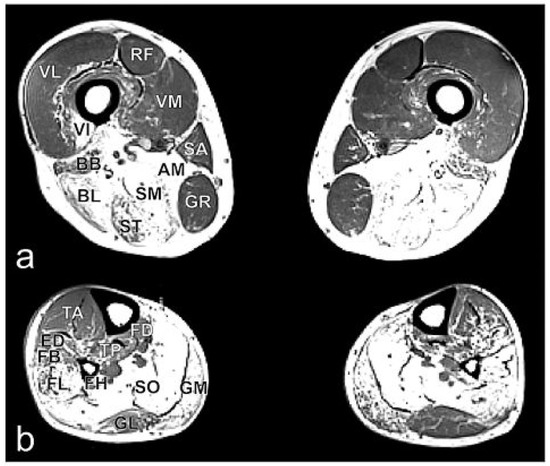

Mapping bioelectric currents with high temporal resolution using magnetic resonance imaging [...] Full article